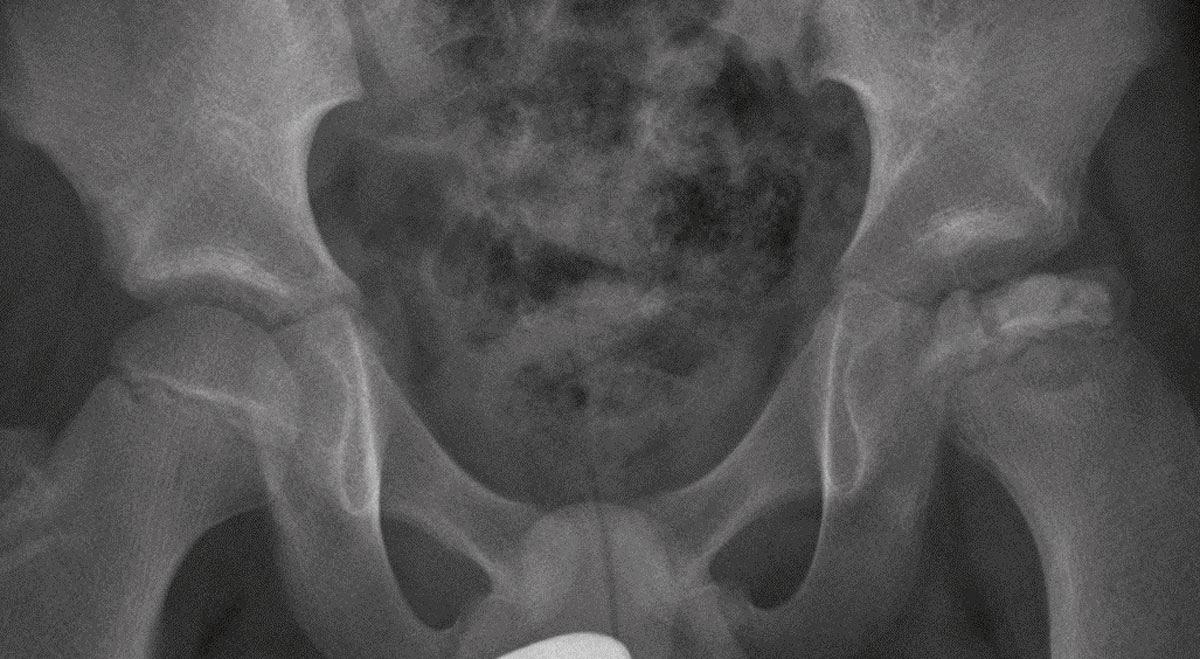

Kinderen met afwijkingen van de heup presenteren zich met uiteenlopende klachten en klinische verschijnselen. De klachten kunnen bestaan uit pijn in heup, bovenbeen, knie of rug, mank lopen, waggelen en andere loopstoornissen en bewegingsbeperking. Mank lopen is meestal het eerste, subtiele teken van heupproblematiek, en gaat vrijwel altijd vooraf aan pijnklachten. Veel orthopedische afwijkingen in de heup worden gepresenteerd met karakteristieke verschijnselen en op een karakteristieke leeftijd. In dit artikel worden de verschillende oorzaken van pijn en klachten rond de heup bij kinderen beschreven. Deze oorzaken zijn in te delen in mechanisch en traumatisch, infectieus/inflammatoir, vasculair, tumoren en niet-orthopedische oorzaken. Hoewel heupklachten bij kinderen als gevolg van trauma’s en sportletsels voor de dagelijkse praktijk van de fysiotherapeut zeer relevant zijn, ligt de focus in dit artikel meer op de specifieke heuppathologie.